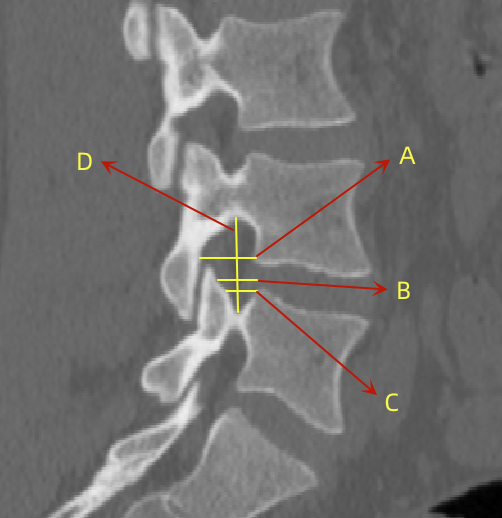

2、通过术前CT测量L4-5节段手术部位的(1)上位椎体后下角水平方向到关节突关节的距离(A);(2纤维环后缘的中点水平方向到关节突关节的距离(B);(3下位椎体后上角水平到关节突的距离C);(4上位椎体的椎弓下切迹与下位椎体椎弓上切迹连线的距离D), 6;(5)在手术节段的棘突矢状位CT层测量椎间隙高度(E), 7;(6)在手术节段的关节突关节横截面CT层测量关节突间距离(F), 8,再通过术中及术后CT判断患者椎间孔成型级别,将A-F测量数据与5级成型中的各级别成型进行相关性分析。

6  A-D的测量方式

undefined